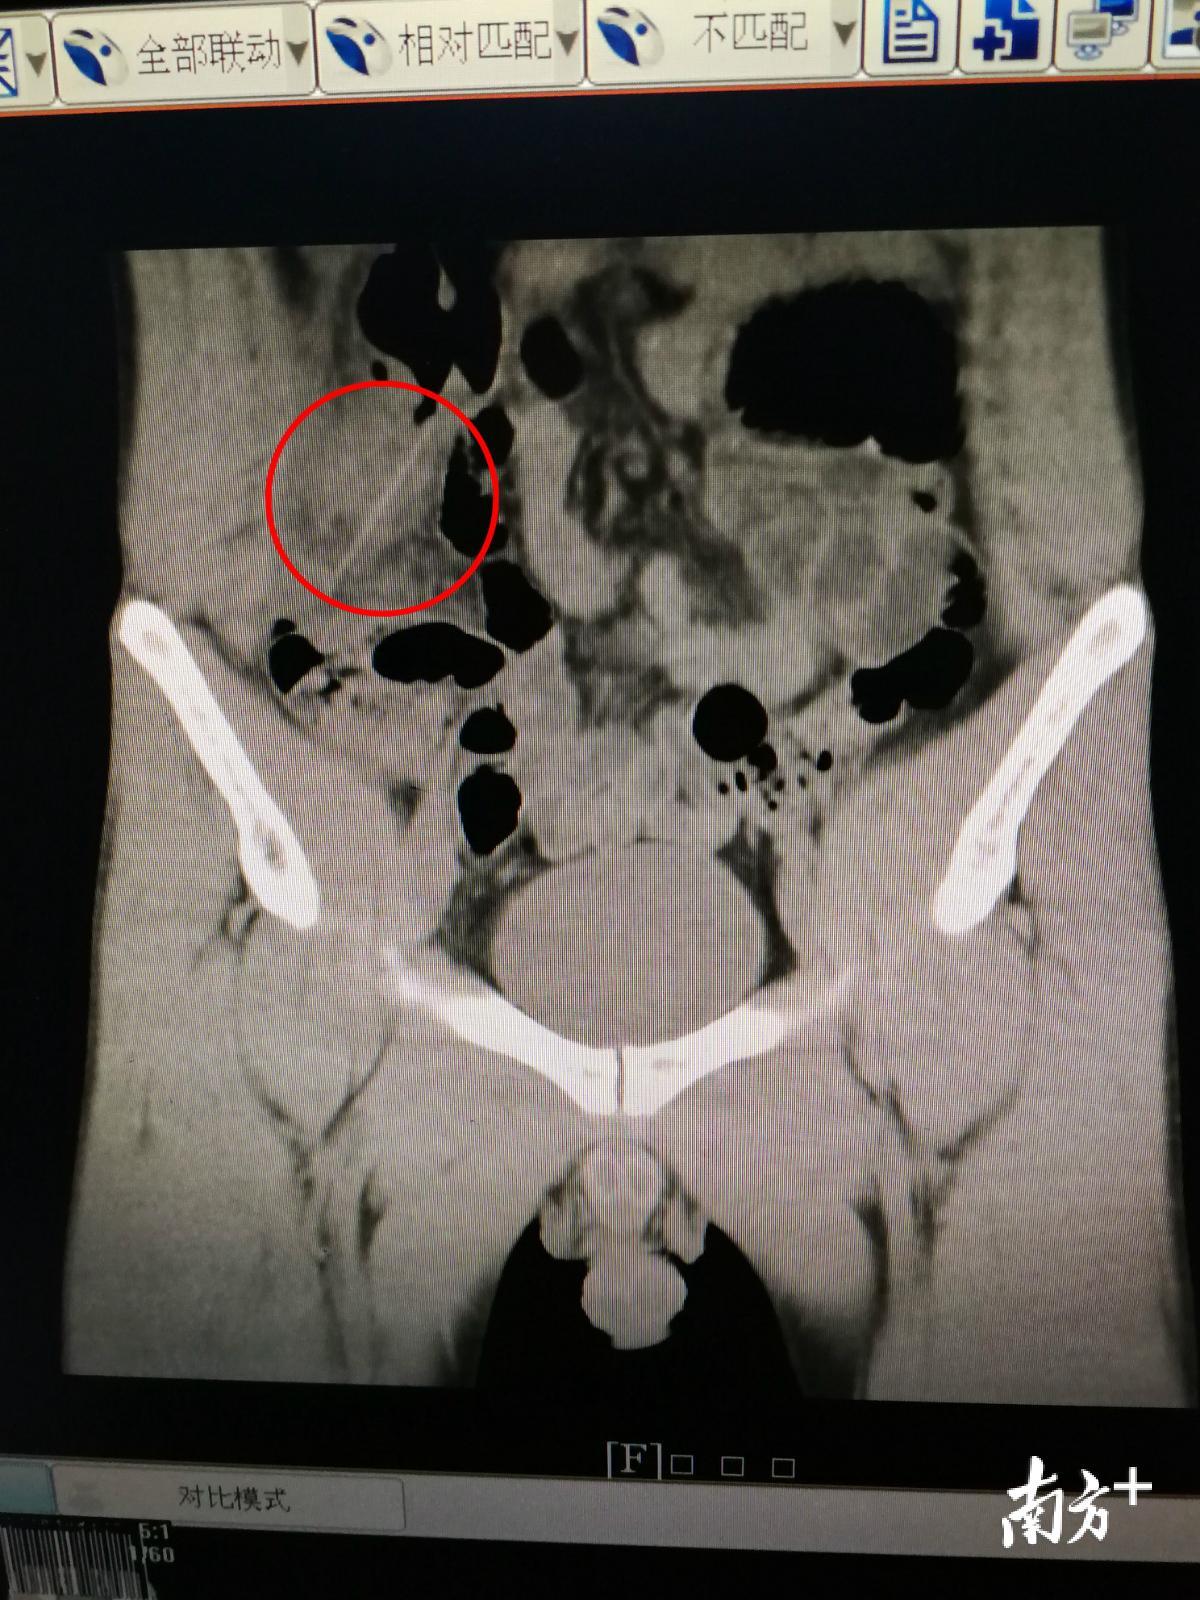

很快,医生立即为邱先生做了下腹CT平扫,CT片显示右下腹有一个长条状异物。考虑当时患者已经出现腹膜炎刺激征,疼痛继续加重,经过科室讨论,医生决定立刻为邱先生进行剖腹探查。术中发现,异物已经穿透了结肠,最终取出的异物竟然是一根完整的牙签。